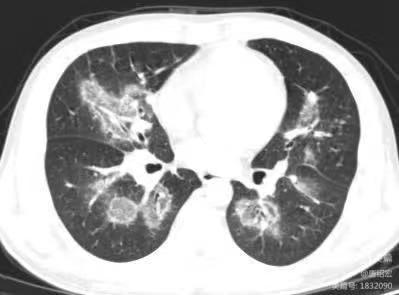

- 反晕征病灶沿气管血管束分布,能分清是沿肺动脉分布?还是沿支气管分布?

临床上围绕血管的渗出非常容易形成反晕征(上图红色箭头),而支气管的渗出不形成反晕征(上图蓝色箭头看似反晕征的中心是支气管,实际上是影像层面显示的原因,肺动脉没有显示出来)。

影像上三种表现形式:1. 单纯的血管侵袭可以出现反晕征(如本例),血管截断征、空洞及实变(但本例未出现);2. 单纯的支气管肺侵袭,出现树芽征(主要特征),磨玻璃影及沿支气管的实变;3. 同时有血管、支气管肺侵袭。